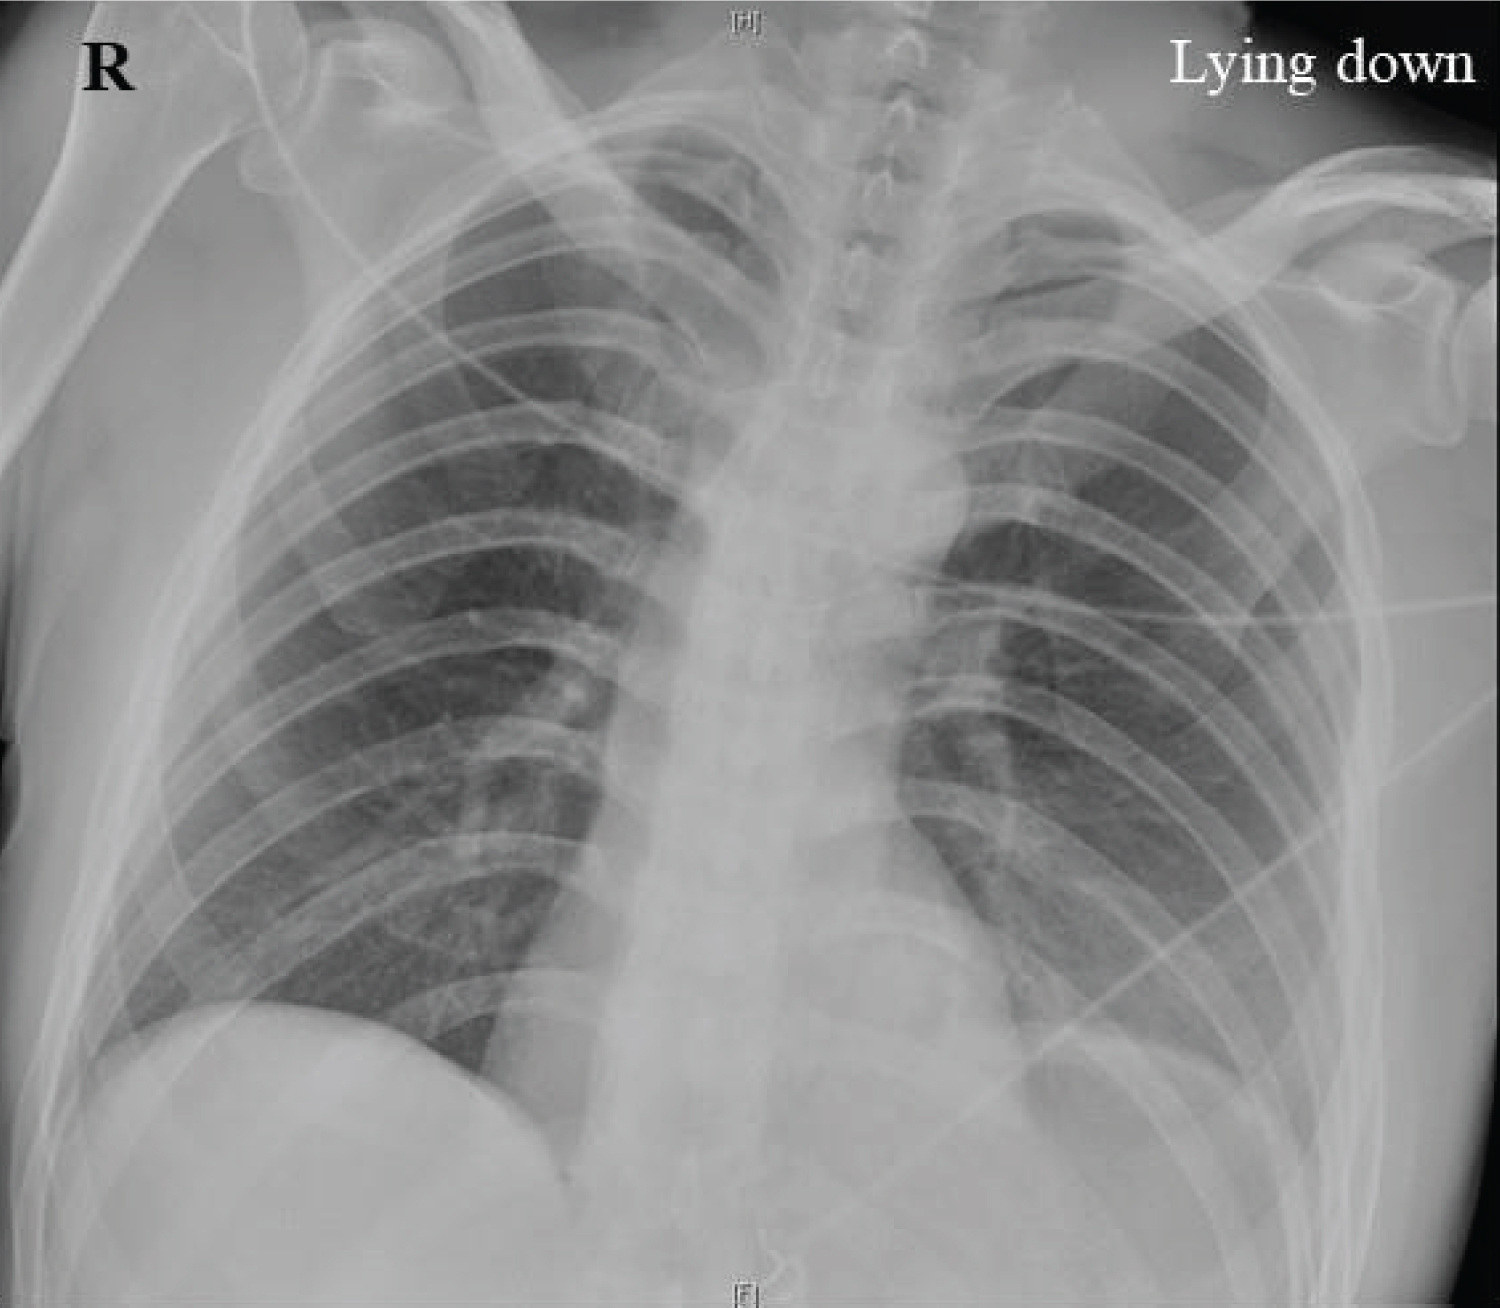

A male ages 40-50 years-old presented to the emergency department with chest pain with radiation for upper abdominal and left flank. As a personal history, of anxiety, in treatment with diazepam and duloxetine. There is no previous relevant history of gastrointestinal disease, and he did not have any preexisting disease and allergic history. His symptoms began suddenly after vomiting and he complained an intense pain (the pain score was 9 out of 10 based on the verbal rating scale). He also reported nausea, diaphoresis, and had no symptoms of severe acute respiratory syndrome. On admission, physical examination showed pale and sweaty skin, his initial vital signs were a blood pressure of 112/73 mmHg, heart rate of 135 beats per minute, respiratory rate of 25 breaths per minute, temperature of 36.2 °C, oxygen saturation 98% on room air. During the initial clinical examination, he was pale and sweaty and very complaining in the retrosternal and left lumbar region. Apart from the above signs, he had no other remarkable findings on systemic examination. A metabolic acidosis with high anion gap (pH 7.37, pCO 2 29 mmHg, pO 2 102 mmHg, bicarbonate 16.8 mmol/L, saturation 98.7%, anion gap of 14 mEq/L, lactate 1.4 mmol/L) was present on his initial blood gas. The initial chest X-ray showed no acute abnormalities Figure 1, most notably no pneumothorax or pneumomediastinum and 12-lead electrocardiogram showed a normal sinus rhythm. The patient's laboratory studies revealed a mild leukocytosis (14 10^3/uL) and C-reactive protein was below 1 mg/L. His renal and electrolyte profile was normal (creatinine of 1.5 mg/dl). There was no abnormal finding by the levels of cardiac biomarkers, pancreatic lipase and amylase, or D-dimer. To clarify the clinical case, a CT was performed, which showed left pneumothorax, anterior pneumomediastinum and indistinct esophageal wall with pneumomediastinum at just above the gastro-oesophageal junction, suggestive of esophageal rupture Figure 2 and Figure 3. General surgery was consulted and due to history of the present illness two sets of blood culture were collected and broad-spectrum antibiotics and antifungals with piperacillin/tazobactam and fluconazole were initiated, as well as analgesia and prokinetics. Faced with the diagnosis of with esophageal rupture, the patient was transferred to a referral center and submitted to surgical repair with placement of an esophageal prosthesis with clinical improvement. He was discharged home on the 12 th postoperative day. After one month’s follow-up consultation, the patient is well with no impairments.

Figure 1: Frontal chest radiograph. View Figure 1